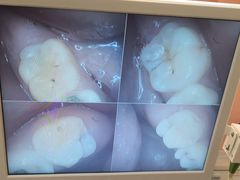

• 牙博士口腔品牌连锁(杨浦店)

• -牙博士口腔品牌连锁(杨浦店)

在云上_7395 | 22-01-04